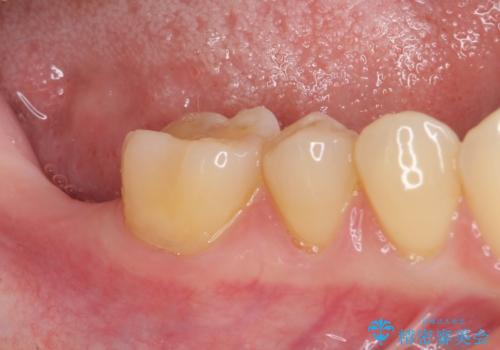

ストローマン社のSLActiveというインプラントを使用し、インプラント埋入からクラウンが装着されるまで3ヶ月弱という短期間で終えることができました。

咬み心地はもちろん、清掃性もご自分の歯とほとんど変わらない状態となり、患者様には大変満足していただきました。